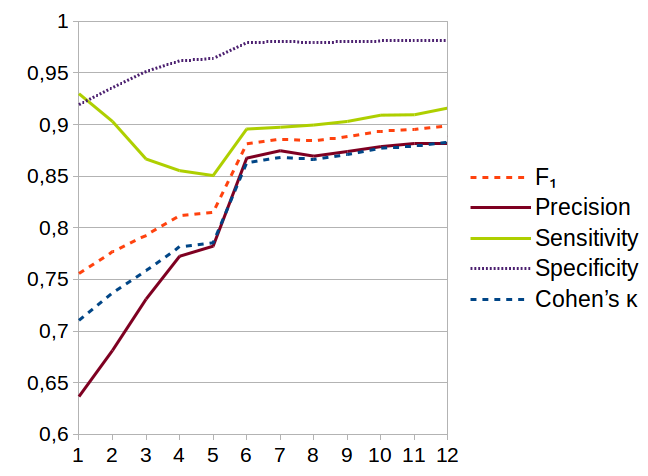

In Fig. 10, we can appreciate the evolution of the method accuracy when sequentially adding features to the gradient boosting classifier. The features are added in the order of importance already shown in Fig. 9.

Table 3 presents the results obtained by evaluating the final mask—provided by the watershed algorithm—against a manually built ground truth. The results are evaluated according to different metrics. We remark the role of the -measure, the harmonic average of precision and recall; and the Cohen’s , which indicates the rate of agreement between the two classes. We consider both of them as being high, in particular when compared to other segmentation tasks.